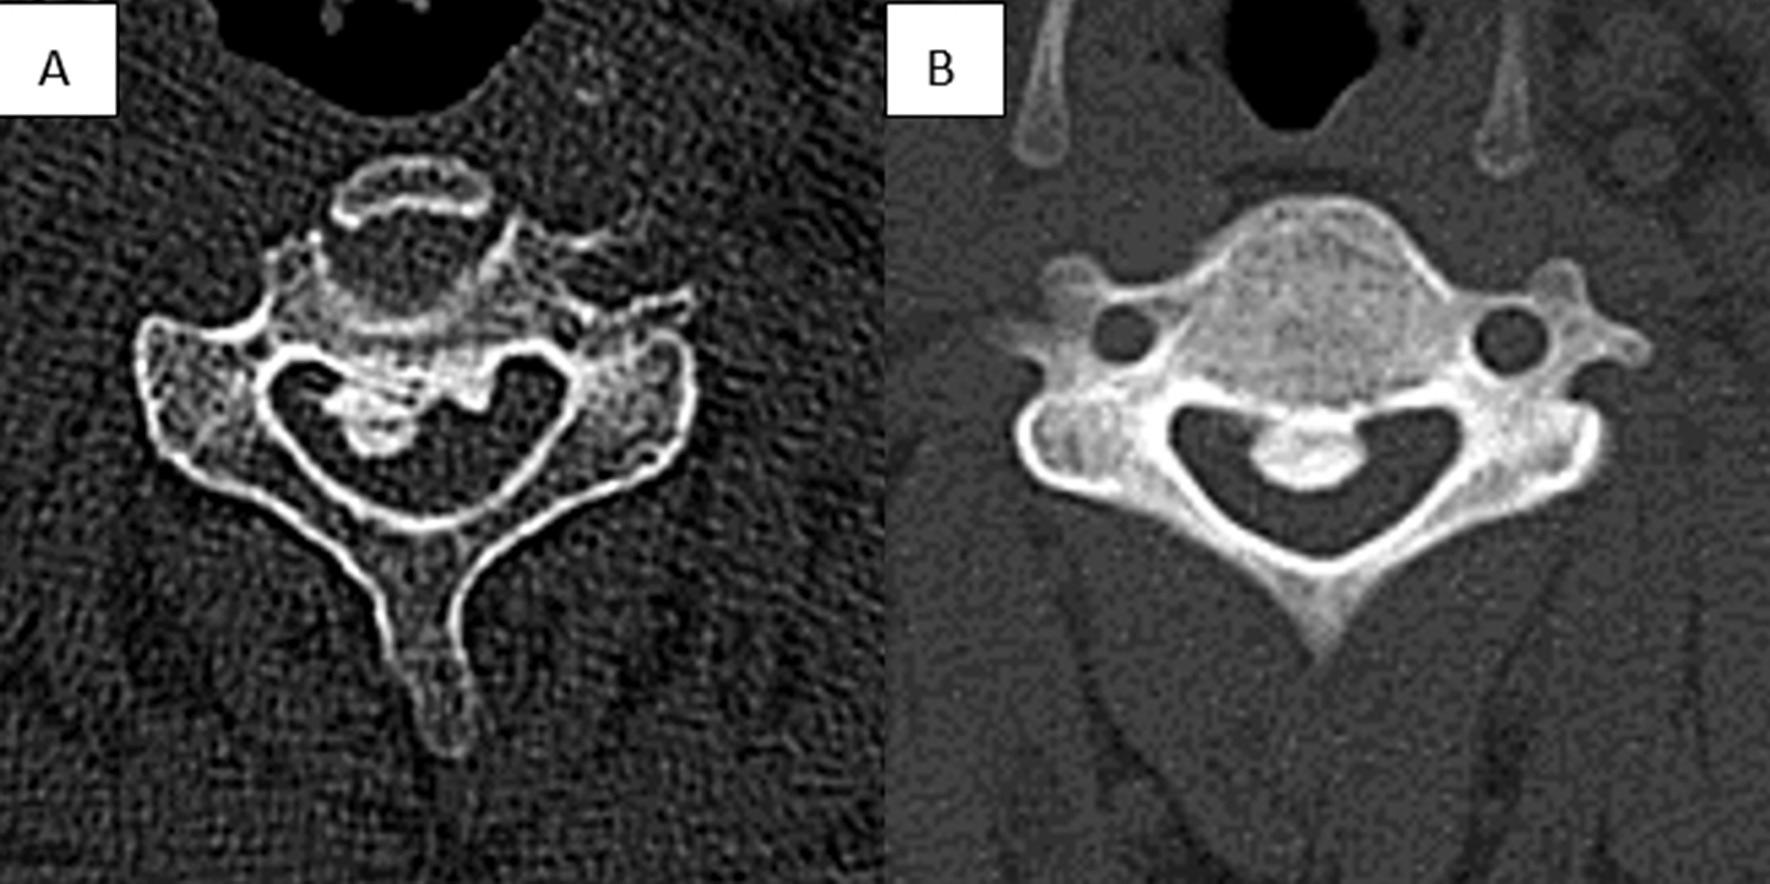

The factors affecting neurological outcomes with unilateral open-door laminoplasty have been controversial. The purpose of this study was to evaluate the impact of the characteristics of ectopic bone on poor neurological outcomes after unilateral open-door laminoplasty.

We retrospectively analyzed the clinical data of 112 patients who underwent unilateral open-door laminoplasty from September 2017 to September 2020. According to the Japanese Orthopedic Association score recovery rate after surgery (Japanese Orthopedic Association recovery rate ≥ 50% and < 50%, respectively), all patients were divided into "poor" and "good" groups. The characteristics of ectopic bone and the position relationship between the open side and ectopic bone (for lateral ossification) in the two groups were compared and analyzed. Univariate and multivariate analyses were used to determine the risk factors for poor neurological outcome.

We identified patients with a mean age of 58.39 years and a mean follow-up of 25.43 months. Sixty (53.6%) patients experienced recovery of poor neurological function. On univariable analysis, significant predictors of poor neurological recovery were occupation rate of spinal canal > 60% (p = 0.000), ossification extending to C2 (p = 0.006), lateral ossification (p = 0.032) and opening side on the ipsilateral side of the ectopic bone (p = 0.011). Multivariate logistic regression analysis revealed that the occupation rate of spinal canal > 60% (P = 0.003), ossification extending to C2 (P = 0.041) and opening the door on the ipsilateral side for lateral ossification (P = 0.013) were independent risk factors for poor prognosis of neurological function.

An occupation ratio > 60% is the most important risk factor. Another one is ossification of the posterior longitudinal ligament extending to C2. Meanwhile, opening the door on the ipsilateral side is indeed a risk factor for lateral ossification. Better neurological function may be obtained by choosing the opposite side of the heterotopic bone as the open side. Therefore, the design of the surgical plan should comprehensively consider these factors.